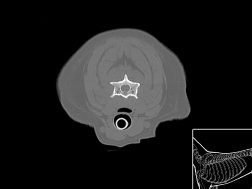

Atlas cérebral du chien SCTO

Scanner tissu osseux

>> 30 coupes

Atlas cérébral du chien SCTM

Scanner tissu mou

>> 30 coupes